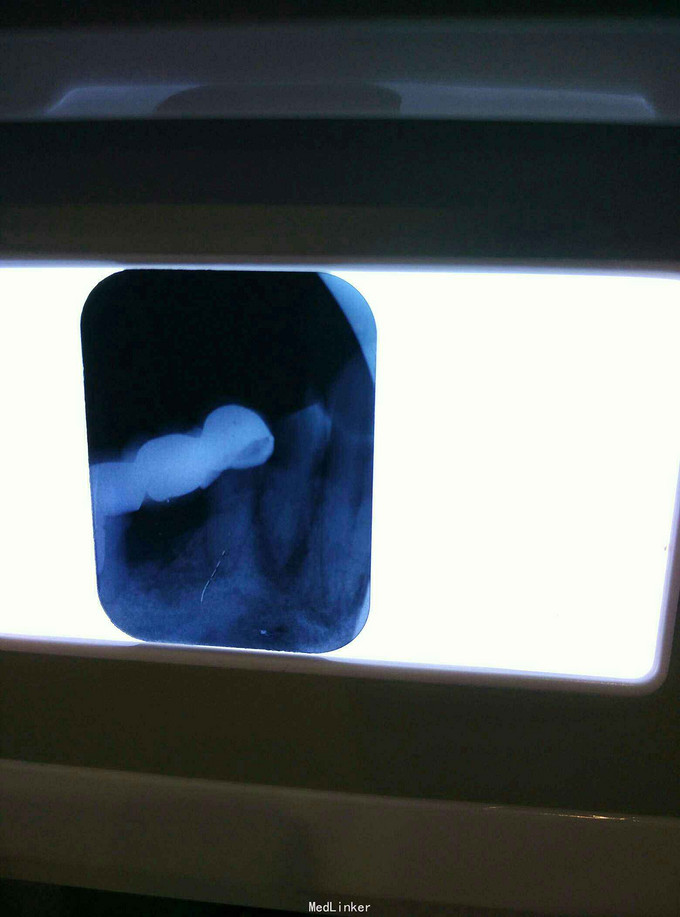

治疗桩冠修复

上左边烂牙嵌塞

根治后桩冠修复

根管治疗+桩冠修复

桩冠修复